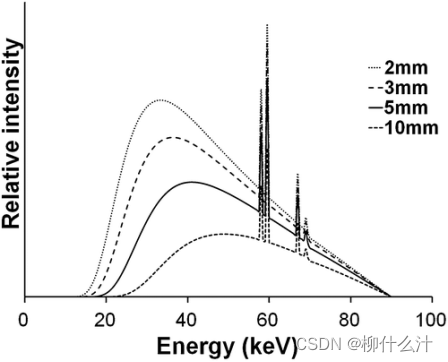

x射线束中的大部分光子是一种叫做制动辐射(Bremsstrahlung)的效应的结果,当从阴极释放并加速向阳极移动的电子与阳极材料发生相互作用是,这种效应就会在x射线管中产生,该材料在一定程度上减缓了电子的速度,根据能量守恒定律,电子动能的损失部分被x射线光子的释放所补偿。Bremsstrahlung光谱通过内部(固有)和外部(添加)过滤进行衰减。在离开X射线管之前,X射线光子将与管壳相互作用,在此期间,主要是低能量的光子被吸收。金属片形式的额外过滤被添加,以确保大多数低能量光子不离开管子,因为这些光子有很大的可能性在病人体内被吸收(即它们对病人的辐射剂量有贡献,但对放射图像没有贡献),CBCT通常使用铝或铜过滤。除了减少入口曝光外,高度过滤的x光线受光束硬化的影响较小。